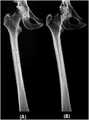

도 19는 부서진 대퇴골의 재건 결과이다.

19 is a result of reconstruction of the broken femur.